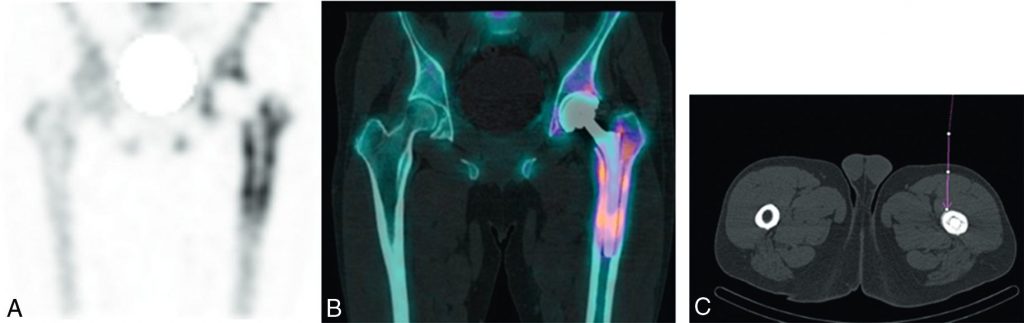

Une scintigraphie osseuse est indiquée en cas de prothèse douloureuse, sans argument étiologique radiographique (figure 82.3). La scintigraphie osseuse n’est en effet pas artéfactée par le matériel prothétique articulaire. Elle peut être couplée à une scintigraphie aux polynucléaires marqués plus spécifique des infections.

Fig. 82.3 Scintigraphie osseuse d’un descellement de prothèse totale de hanche gauche.

Clichés tardifs en coupes coronales TEMP (A) et TEMP-TDM (B) mettant en évidence une hyperfixation périprothétique diffuse de la pièce fémorale associée à une apposition périostée (flèche) sur la coupe TDM axiale (C), en faveur d’un descellement.

Source : CERF, CNEBMN, 2022.

Une hyperfixation périprothétique intense oriente sur le site du descellement (septique ou non) (cf. figure 82.3).

- Une hyperfixation focalisée oriente vers un éventuel foyer de fracture.